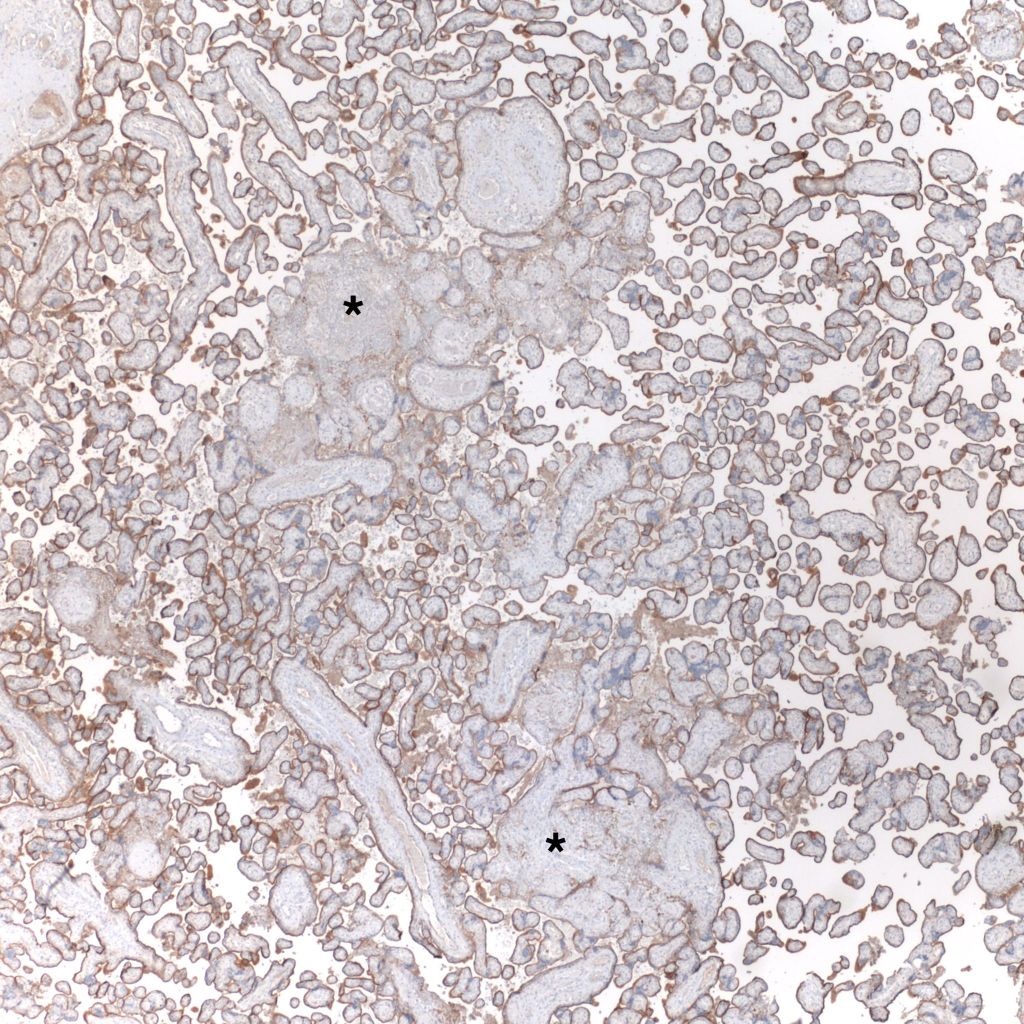

Low Grade CHIV (5-50% of the intervillous space occupied by monocytes)

There is a focus of intervillous fibrinoid with no definite cytotrophoblast that is not re-covered with syncytium suggestive of recent syncytial injury (F). (10x, H&E)

CD68 or alkaline phosphatase: to confirm that the intervillous cells are monocytes, but is not required for meeting the diagnostic criteria